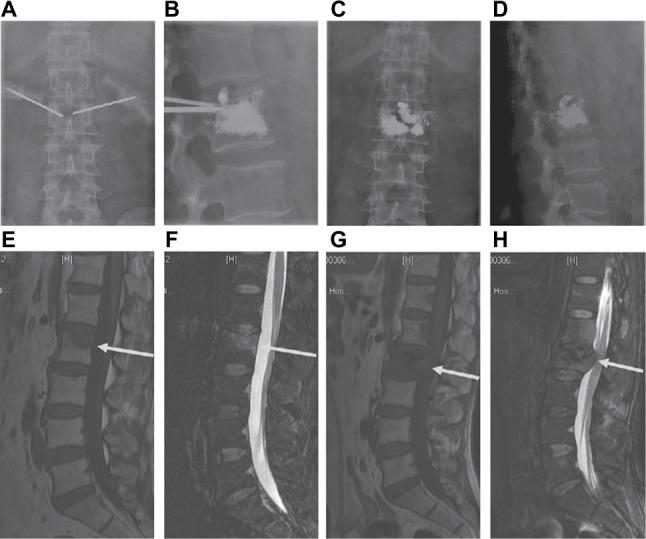

A total of 124 patients were selected for PVP and ITR (n = 71, group A) and PVP alone (n = 53, group B). A 14 G needle and guide wire were inserted into the vertebral body, followed by sequential dilatation of the tract until the last cannula reached the anterior portion of the pedicle. Tumors were then ablated with a radiofrequency probe. ITR was performed with marrow nucleus rongeurs, and then cement was injected into the extirpated vertebra. Outcomes were collected preoperatively and at 1, 3 and 6 months and every subsequent 6 months.